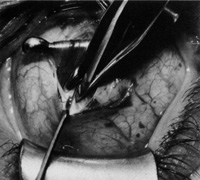

Step 1. The lateral rectus muscle is isolated through either a limbal (Fig. 1) or fornix incision. The muscle is dissected free of intermuscular septum and check ligaments for a distance of approximately 15 mm posterior to its insertion. When a fornix approach is used, the procedure can be performed through a single inferior temporal incision; however, making a second superior temporal fornix incision facilitates reattachment of the superior arm of the muscle.

Fig. 1. The lateral rectus muscle is isolated through a limbal incision and dissected free of intermuscular septum and check ligaments for a distance of approximately 15 mm posterior to its insertion.